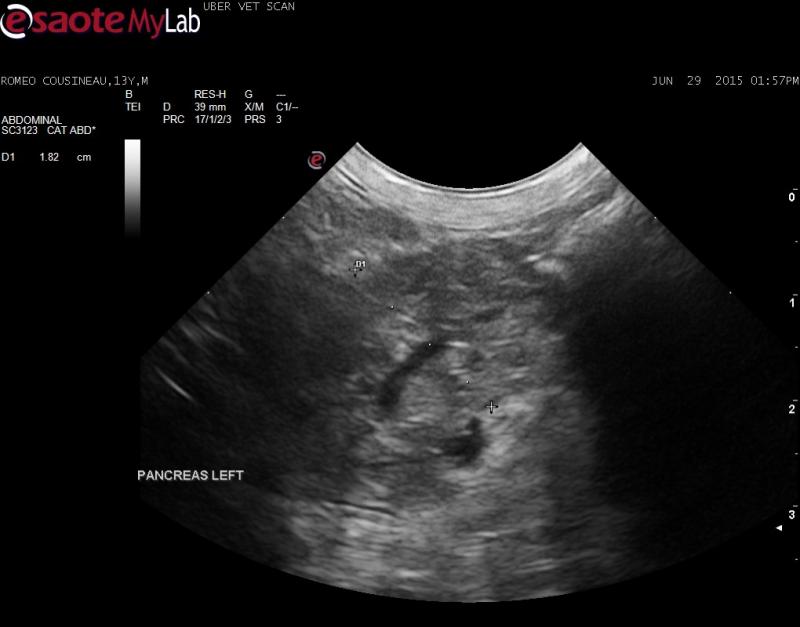

– left pancreatic limb is enlarged and mottled

There are a lot of them in th eliver but they are more consistent with biliary adenomas…that can transform into adenoca so worth watching, The pancreas has a straight panc duct wihtout disrup[tion or deviation which suggests chronic pancreatitis or hyperplasia nad not carcinoma. The LN is ovoid and echogenic not distroteed which suggests inflammatory. Lots to talk about but I am giving benefit of the doubt on this guy. Screening fna panc ln and liver nodules to enhance the suggestive for “benign.”